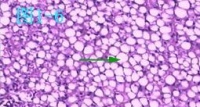

- 脂肪变脂肪变(Fat change或steato)指中性脂肪尤其甘油三酯蓄积非脂肪细胞中;多发生于肝细胞(最常发生)、心肌细胞、肾小管上皮细胞;镜下观:细胞呈空泡状;肉眼观;受累器官体积增大、淡黄色、边缘圆钝、切面油腻;如脂肪肝、虎斑心(注意与心肌脂肪浸润相鉴别);